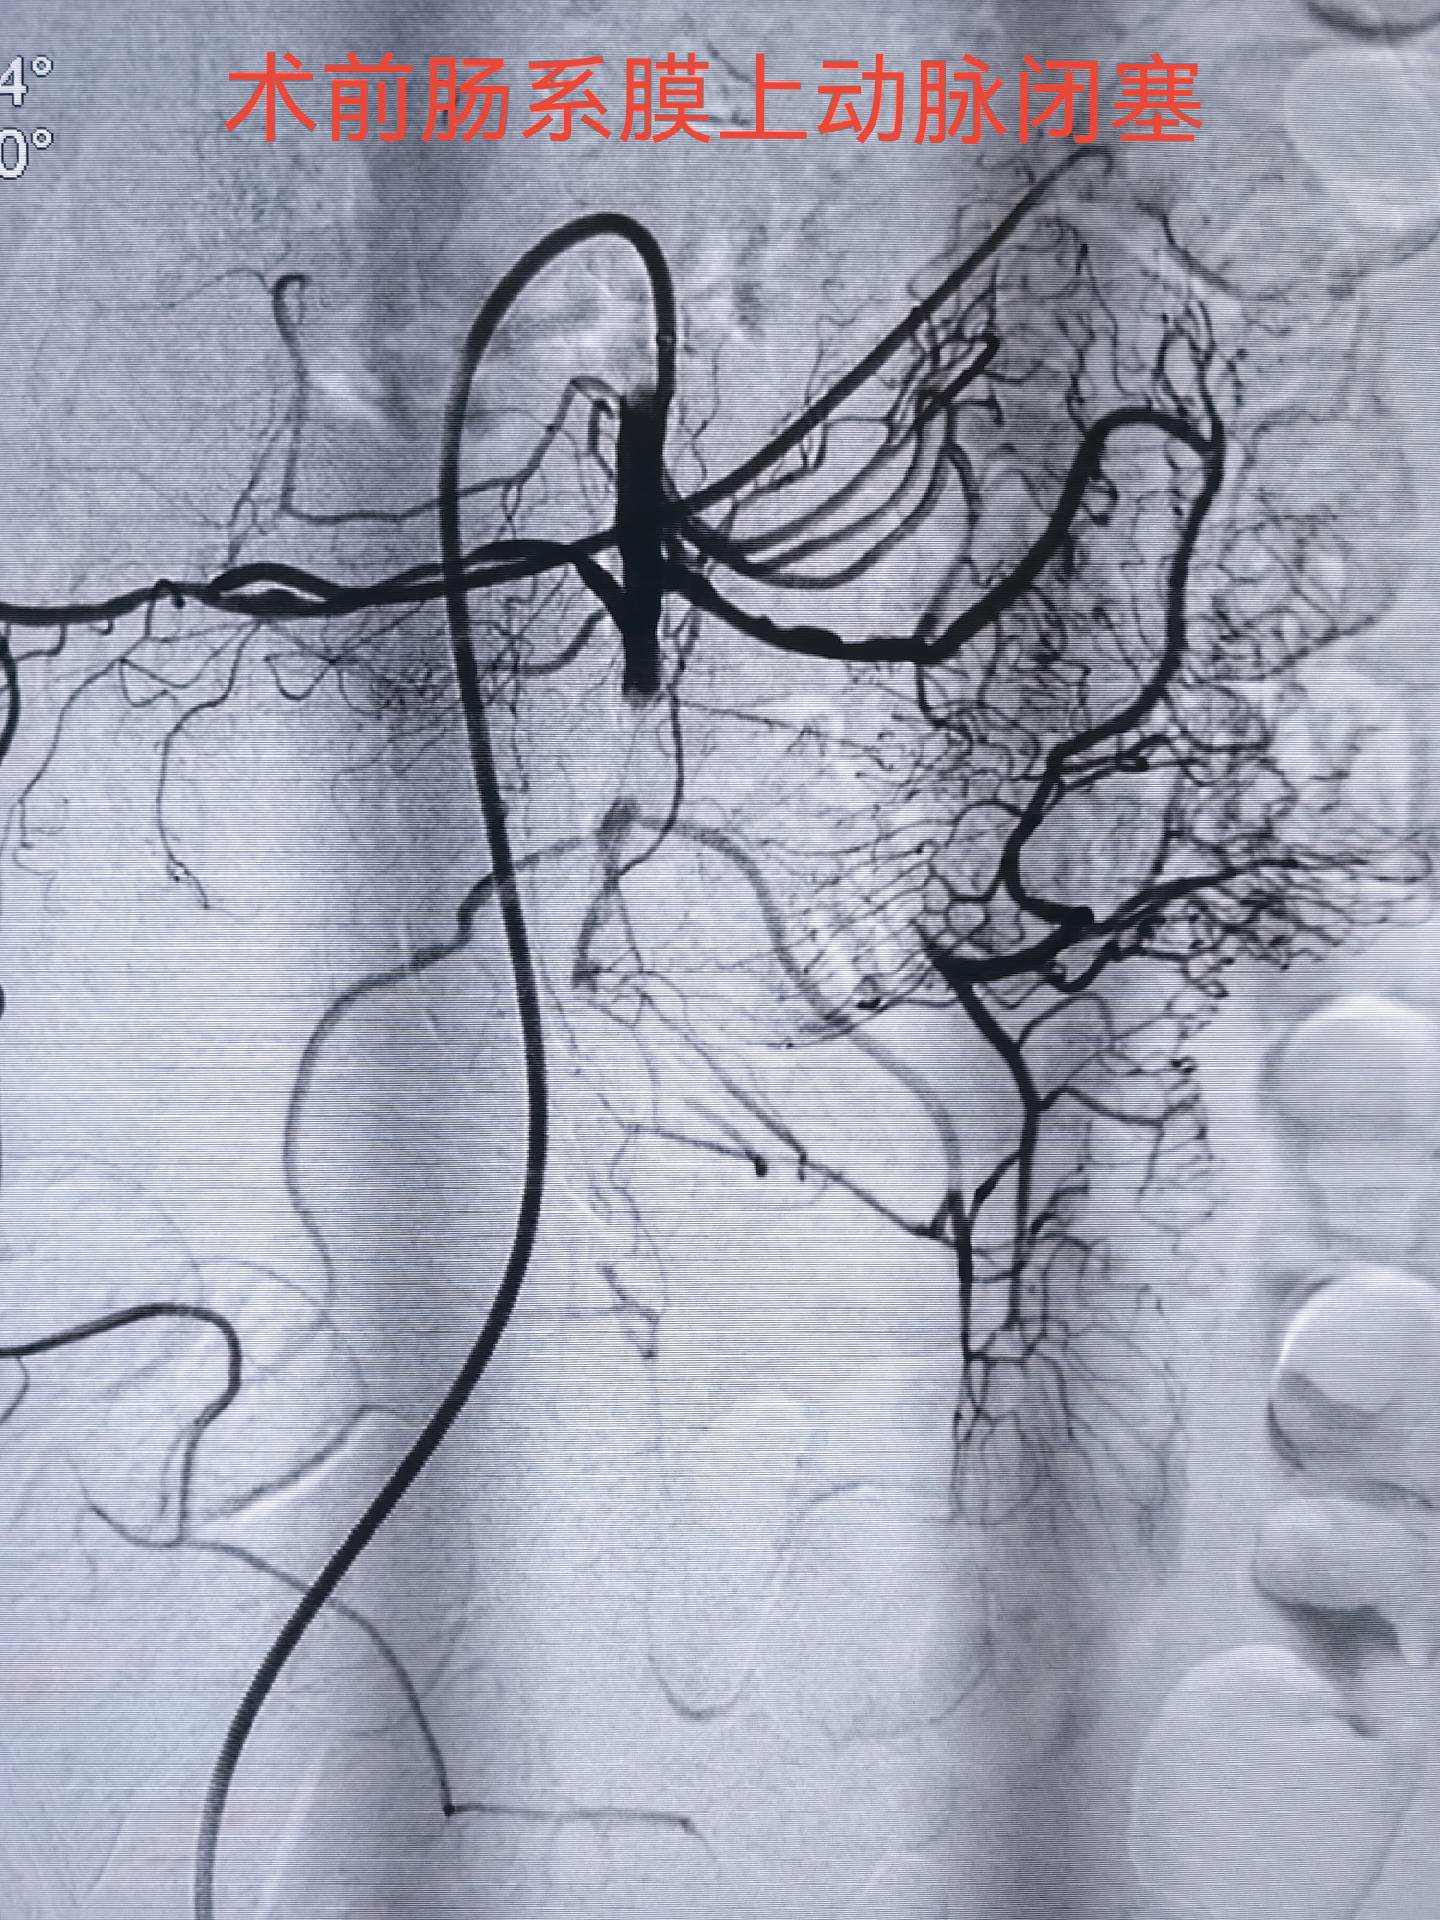

肠系膜上动脉栓塞,会导致肠缺血坏死危及生命,急诊介入开通挽救